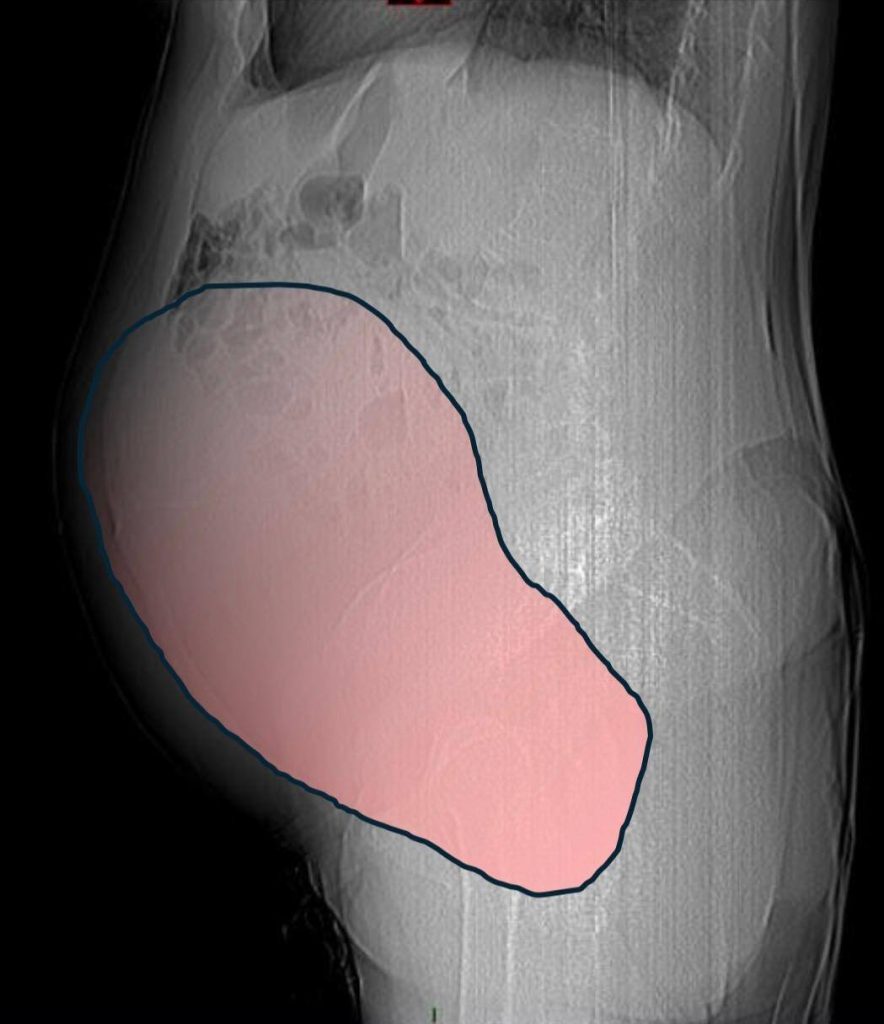

In a complex operation lasting around six hours, surgeons successfully removed the 28cm (1 in) tumour, which weighed a staggering 6kg (13lb).

The growth was described by the City of Health and Science of Turin as “comparable in volume to a full-term twin pregnancy”.